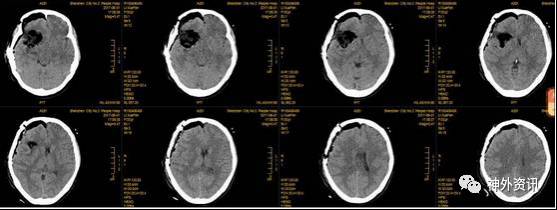

术后影像

术后CT